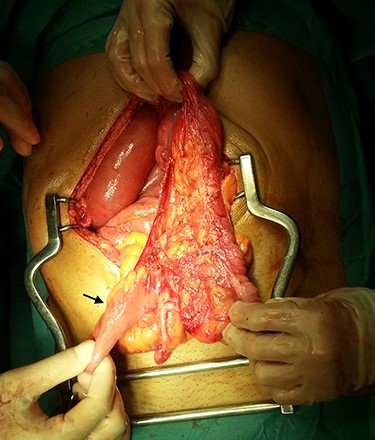

In the presence of an intestinal obstruction of an unclear cause, an exploratory laparotomy was proposed. A peritoneal encapsulation (Fig. 4) of the small bowel was identified, without intestinal ischemia. The peritoneal sac was located in the right abdominal quadrants, only partially involving the small bowel, so in the left quadrants there was normal caliber ileum externally to it. The membrane was excised and the peritoneal cavity was explored, showing signs of intestinal malrotation with medialization of the right colon (Fig. 5) and a retrocecal position of the terminal ileum leading to intestinal obstruction (Fig. 6). After lysis of adhesions from the bowel to the membrane, the terminal ileum was released and complementary appendectomy was done. Histopathology revealed normal peritoneal tissue. After prolonged ileus, patient was discharged on the 8th postoperative day and presented asymptomatic 1 year later.

After excision of the accessory peritoneal membrane, signs of intestinal malrotation with medialization of the right colon were noted (arrow).